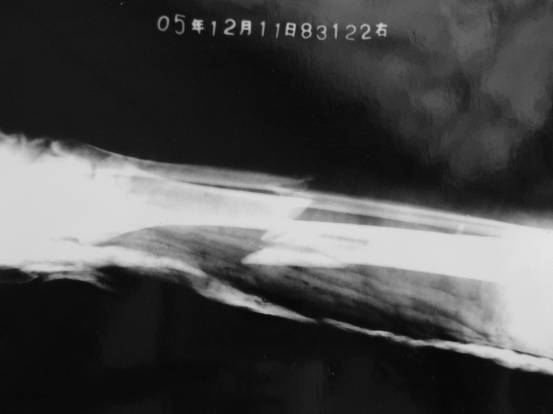

2:再附龚星灿被迫害前与第一次被非法劳教迫害,造成胫腓骨粉碎性骨折保外就医时的前后照片对比(见图片);以及骨折的X光照片(见图片),当时骨头刺破外表皮肤十多公分,缝合了十几针,直到再次被绑架关押时,还有二公分表皮没有好。

骨折的X光照片